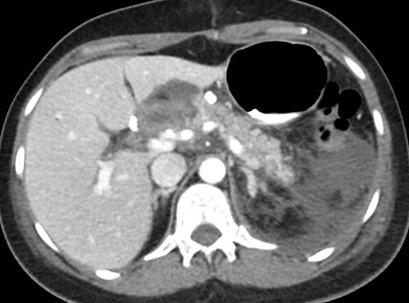

Paciente masculino de 35 años de edad, con antecedentes de tabaquismo, etilismo, consumo de sustancias psicoactivas. Ingresa al hospital de Sanatorio Franchin el 24 de mayo de 2024, donde se constata hipoglucemia severa con buena respuesta al glucosado hipertónico endovenoso. Al examen físico con la típica tríada de Whipple, dado por síntomas neuroglucopénicos de alteración del estado de conciencia, glucemia de 25 mg/dl y alivio sintomático después de la administración de glucosa. El paciente recupera el estado de conciencia y refiere dolor abdominal a nivel de epigastrio, por lo que se le realiza ecografía abdominal, donde se evidencia lesión nodular hipoecogénica en cuerpo del páncreas. Por esta razón se pasa al paciente a tomografía, donde se constata una formación nodular a nivel del cuerpo del páncreas, que presenta un ávido realce en fase arterial con homogeneización de la lesión en tiempo tardío.

Ahora bien, como se mencionaba al principio, el estudio ecográfico es de muy baja sensibilidad y se identifique o no la lesión por este estudio, nuestro siguiente paso en el algoritmo diagnóstico de esta lesión es la tomografía. Esta es la prueba no invasiva inicial, con una sensibilidad del 63% al 83%, y detecta del 70% al 80% de los tumores. Esta debe realizarse como un estudio trifásico: fase arterial temprana a los 30 segundos, fase venosa a los 70 segundos, fase tardía de 3 a 5 minutos. La característica de estos tumores por tomografía es que se presentan como una masa sólida que tiene un ávido realce en la fase arterial, cuyo realce se mantiene y se observa más tenue en la fase venosa y en los tiempos tardíos la lesión se homogeniza.

Para mi caso, y dando una visión general de los métodos de imagen no invasivos en esta revisión retrospectiva, solo a uno de los pacientes se le detectó la lesión por ecografía, donde se visualizó una lesión nodular hipoecogénica en el cuerpo del páncreas. A los demás pacientes se les detectó la lesión por tomografía en estudio trifásico, donde resaltan las características ya descritas por la literatura de lesiones hipervasculares con intenso realce en fase arterial, localizadas en diferentes partes del páncreas, como cabeza, cuerpo y cola.